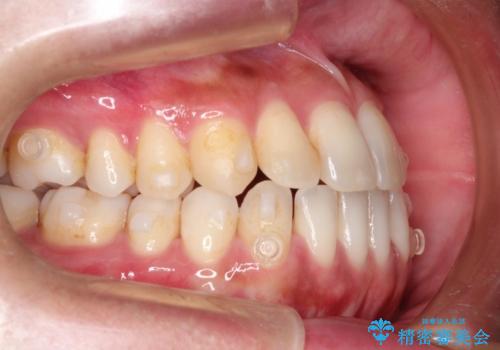

Invisalign インビザライン によるガタつき、受け口傾向の改善

- 拡大・IPRによるスペースゲインを主とした非抜歯・マウスピース矯正を計画しました。

奥歯の位置関係の修正は難儀することが多いマウスピース矯正ですが、割とスムーズに奥歯の位置関係の修正をすることができました。

クロスバイトもきれいになり、きれいな歯並びとなりました。